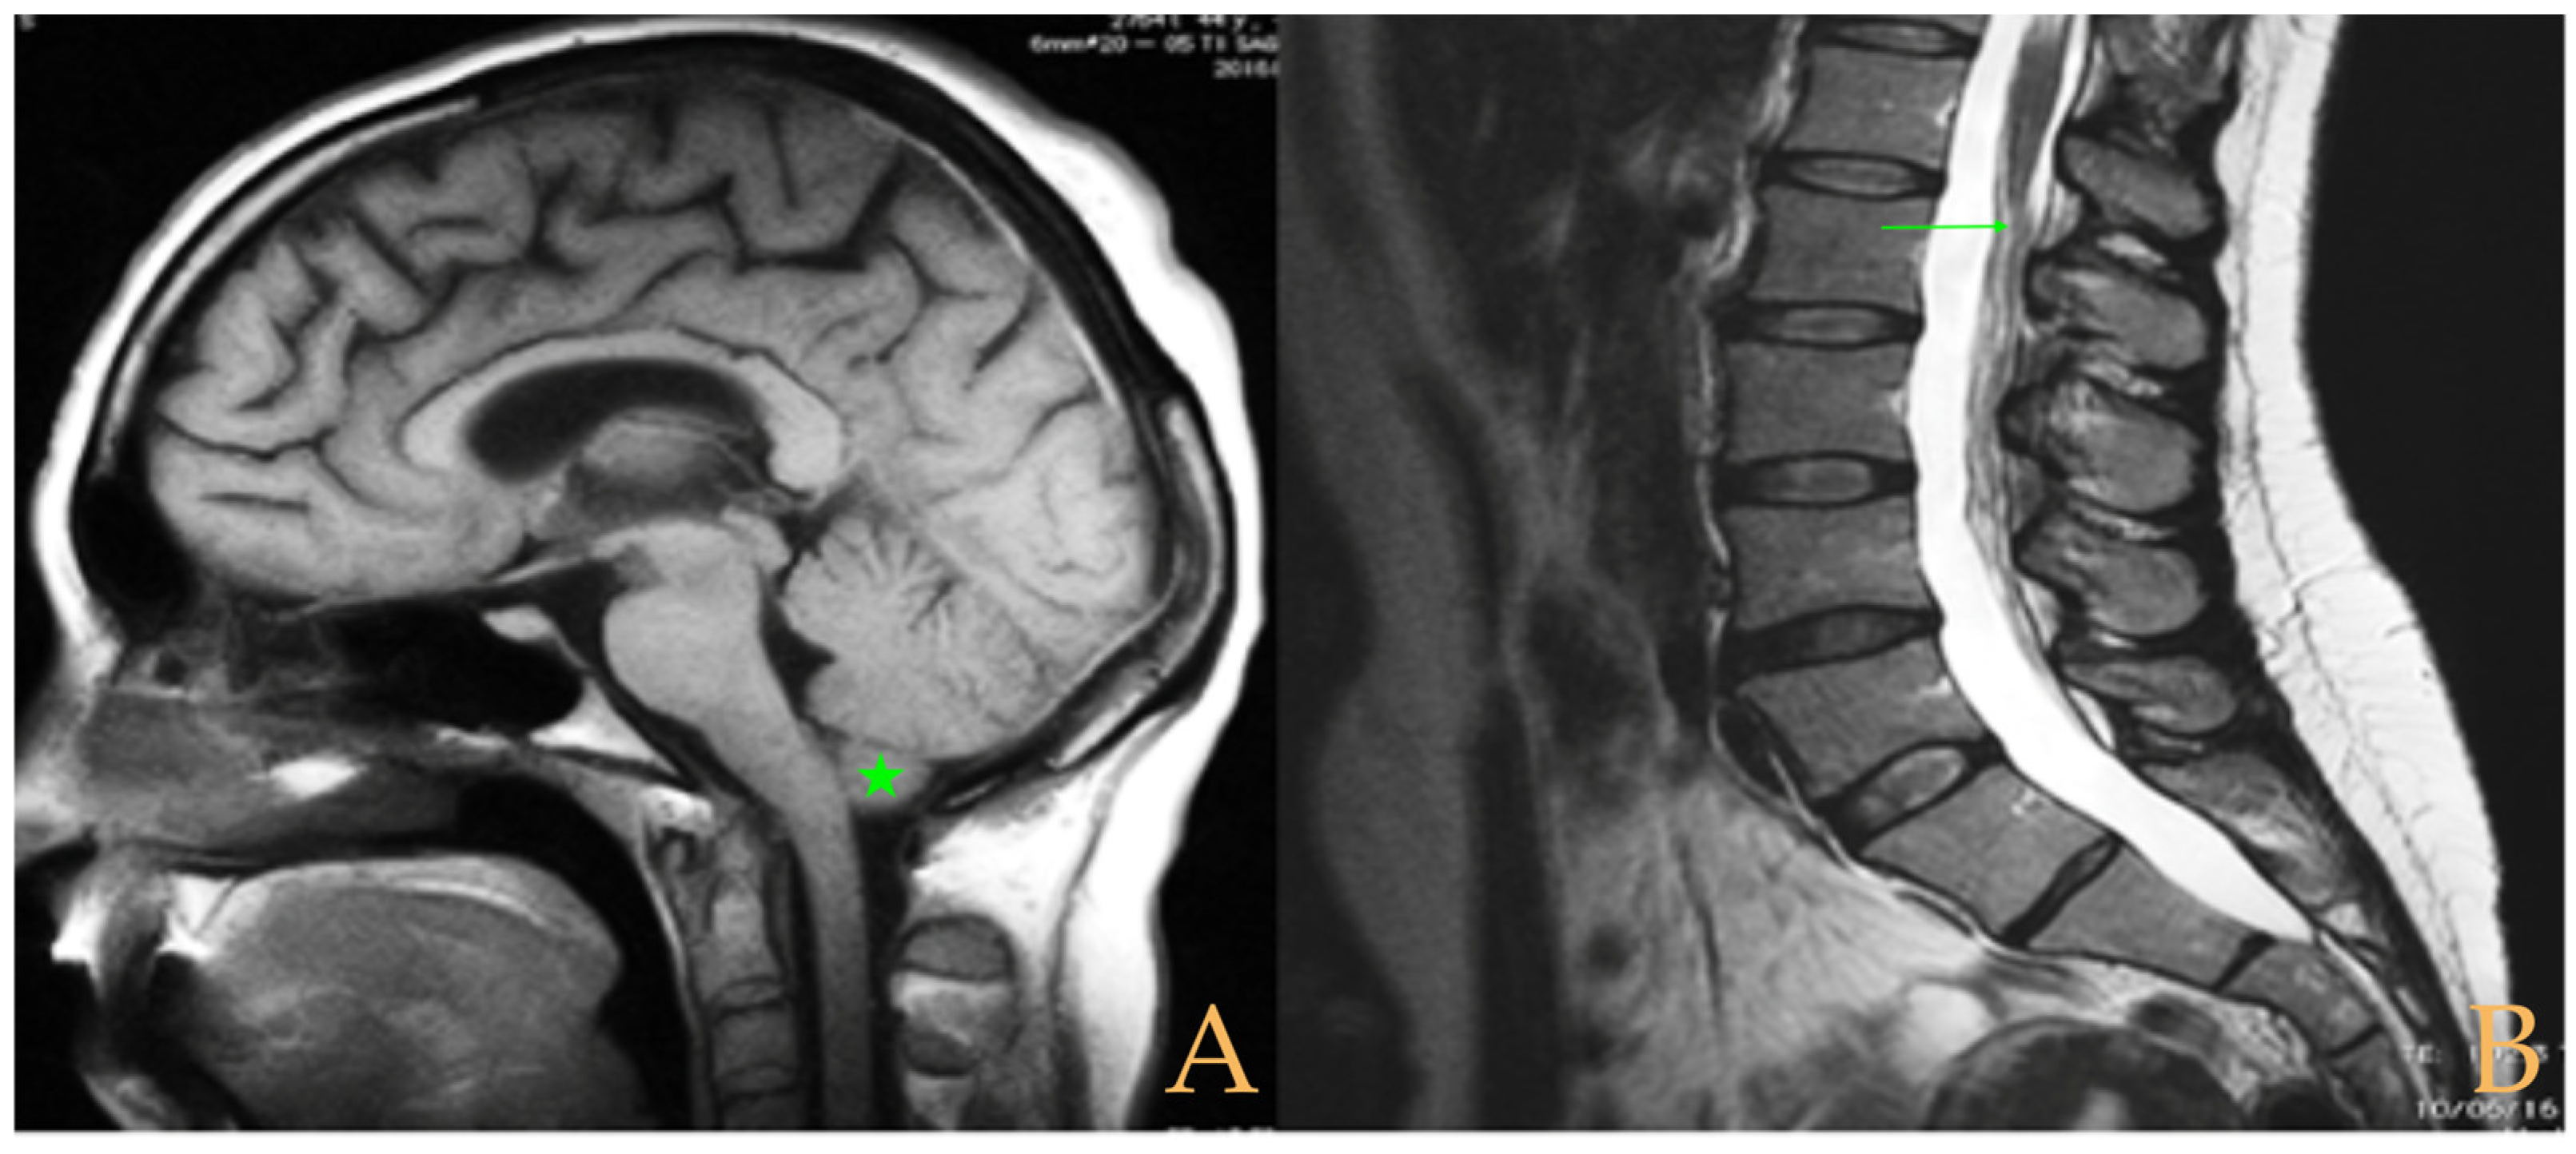

The MRI showed a descent of the cerebellar tonsils, increased supracerebral space, and micro lacunae in the bilateral white matter and the left basal ganglia. Upper cervical kyphosis and straightening in the lower levels. Surgical arthrodesis at C4-C5 and C5-C6. Cervical, thoracic and lumbar protrusions. Ischemia and oedema in the cervical and thoracic spinal cord. Slight cervical rotoscoliosis. Disc protrusions: T7-8, T11-L1, L2-L3-L4, and disc herniation L4-L5. Loss of the lumbar lordosis. Conus medullaris at the level of the middle third of the L1 vertebra (Figure 2). The X-ray images of the entire spine showed levoconvex thoracolumbar scoliosis of 21°, dysmetria of the lower extremities with shortening of the right lower extremity by 10 mm, with respect to the level of the hip, and 99 mm at the level of the iliac crests, 16° cervical lordosis, 49° thoracic kyphosis, and 59° lumbar lordosis.

Figure 2. Imaging of patient 2. A: Image suggestive of spinal cord ischemia (arrows), impaction of the cerebellar tonsils (star), and straightening of the cervical spine (interrupted line); B: straightening of the upper part of the lumbar spine (interrupted line) and conus medullaris at the level of the L2L3 disc space (arrow); and C: brain MRI with micro lacunae in the white matter (arrows).